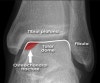

진단

X-ray 사진에서는 간과되는 경우가 많습니다.

그러나 골연골병변을 염두에 두고 호발부위인 내측, 외측의 귀퉁이를 전후상으로 신중하게 검색하면 많은 경우 X-ray 사진에서도 발견할 수 있습니다.

진단이 어려우면 MRI가 진단에 유용합니다.